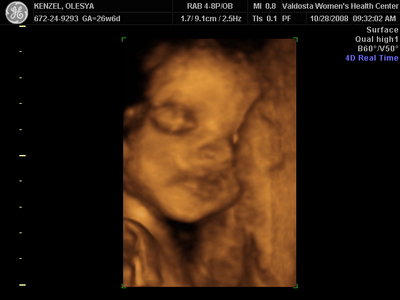

Еще одна Джианнка:

KENZEL,OLESYA_5.JPG [ 60.02 КБ | Просмотров: 1507 ]